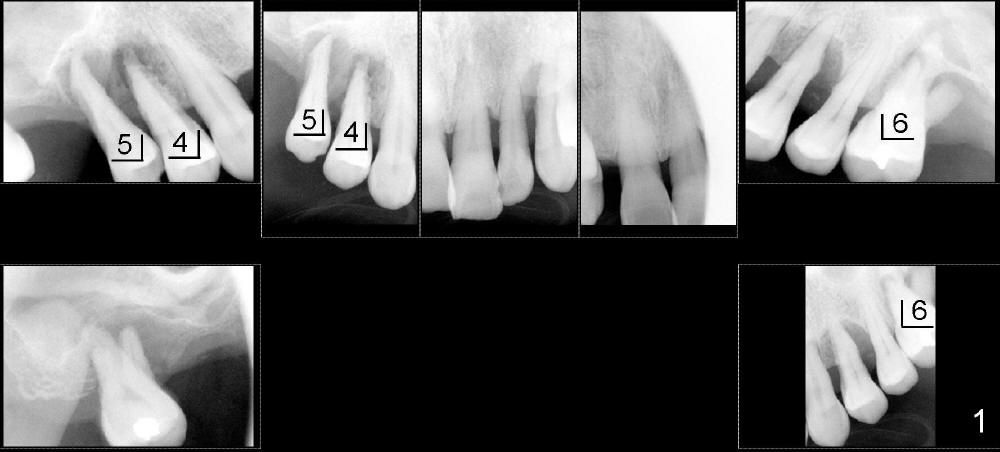

五十来岁吴先生牙周病严重(图一),尤其右上4,5,左上6,最后拔除(图二:远中面观),可见口腔卫生差。先做局部托牙,三年后又失去几个下牙,终于同意植牙。主要困难是上颌窦很低,最好先做上颌窦植骨,但是他胆子特小,多做一个手术对他来说是很大精神创伤,所以壮着胆子先做左上6植牙(图五:7x11mm,torque > 60 Ncm),虽然远中底板不可观(图五箭头之间),但是植牙很牢靠。右侧上颌窦底板更薄,估计不做上颌窦植骨不行,给他吹风说需要做一个手术才能植牙,他竟然同意。但是突然他的托牙(framework removable partial denture)断裂了,断在金属部分(major connector: anterior and posterior bars),说明他咀嚼力如此大,技工室说激光焊接没有保证。我们不得不取消上颌窦植骨,因为它会延迟植牙五六个月,所以我们再次铤而走险在右上第一双尖牙(图三:4, 4x20mm,> 60 Ncm)和第一磨牙(6, 6x11mm,> 60 Ncm)植牙,一个月后在两者之间再植入一个(图四:5,4.5x14mm,> 60 Ncm)。尽管第一磨牙植牙远中骨板相当薄(图四箭头之间),但是它很紧,可能与上颌窦底板坚硬有关。在病人多次要求下,半个月后就装上基牙(图六:2,4,5,6),放置临时牙冠,后三者连在一起(好像牙桥,增加稳定性),这样病人可以正常吃饭。一周后,侧切牙临时牙冠脱落,病人回诊所重新粘固,而右上牙桥仍稳定。